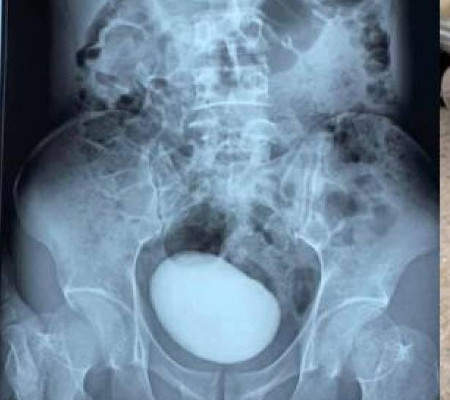

Mulher com dores descobre pedra de quase meio quilo na bexiga | Foto: reprodução

Uma foto de uma pedra gigante que foi retirada da bexiga de uma mulher está causando furor nas redes sociais. Segundo o Clarín, tudo começou quando a vietnamita de 34 anos foi à emergência de um hospital em Thay Nguyen, no Vietnã, se queixando de fortes dores abdominais. Informações do Metro.

Após perceberem que seu abdômen estava mais duro que o normal, os médicos decidiram fazer uma tomografia computadorizada para obter uma imagem do que estava lá dentro. O que eles não esperavam, entretanto, era encontrar uma enorme massa redonda alojada em seu abdômen.

Ela teve que ser submetida a uma cirurgia de emergência para remover a pedra de mais de dez centímetros de comprimento e 400 gramas. Nas redes, onde o caso viralizou, muitos usuários comentaram que não acreditam em como a mulher conseguiu levar uma vida relativamente normal e por tanto tempo com uma pedra dessas alojada em sua bexiga.

De acordo com um estudo publicado em 2014 por uma revista especializada em urologia, cálculos com mais de 100 gramas são muito raros, com menos de 85 casos registrados e documentados ao longo dos anos. Além disso, a pedra da mulher é a mais longa já extraída.